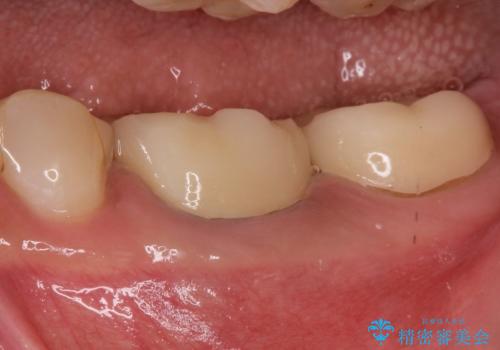

【メタルフリー】オールセラミッククラウン

オールセラミッククラウン(st)にて修復しております。

根管治療も合わせて行なっているため、期間がかかっております。